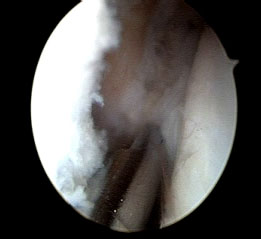

Arthroscopy is a “keyhole” operation that is used to look inside and treat joints, i.e. knee joint. The word arthroscopy comes from two Greek words, “arthro” ( joint) and “skopein” (to look). The term arthroscopy means “ to look within the joint”.

It is performed through a very small incision in the skin, using a narrow telescope attached to a video camera. Compared to open surgery, which involves a larger incision. Keyhole surgery and is less painful, carries less risk of infection, and enables people to recover more quickly.

An arthroscopy may be used to investigate ankle problems, treat conditions such as inflammation, take small samples of tissue or repair damage to tissues and cartilage. The procedures can be done as a day case – without the need for an overnight stay in hospital.